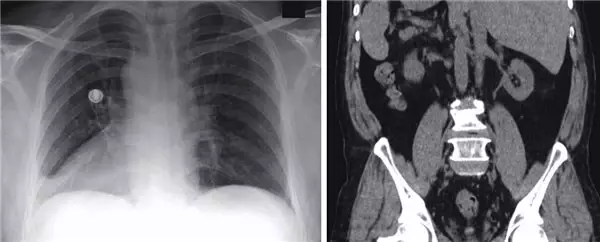

Keşfedilen son vakada, 66 yaşındaki bir adamın bütün organlarının ters tarafta olduğu ortaya çıktı. Öksürük ve göğüs ağrısı şikayetiyle hastaneye giden adamın, yapılan incelemelerde organlarındaki gariplik dikkat çekti. Bilimsel olarak situs inversus totalis adı verilen bu durum, kişilerin hayatına çok da etki etmiyor. Aslında, modern teşhis yöntemleri gelişene kadar bu durum hiç fark edilmemişti.

Yapılan incelemelerde, ABD'ye göçmeden önce 20 yıl boyunca sığınmacı kampında yaşayan adamın kalbinin sağda olduğu, diğer organların da ayna simetrisine göre yerleştiği ortaya çıktı. Yani normalde sağda olan karaciğeri solda yer alıyordu.

Adamın hastalığının ise basit bir üst solunum yolu rahatsızlığı olduğu ortaya çıktı. Basit bir ilaç tedavisi uygulanan adam daha sonra taburcu edildi. Situs inversus totalis, organların yerlerinin farklı olduğu vakalar arasında en yaygını ve kabaca her 10 bin kişiden 1'inde görülüyor.

Organların konumlarındaki farklılık, tek bir organın, örneğin kalbin, olması gereken konumdan başka bir yerde olması durumunda ölümcül hale gelebiliyor. Modern teknoloji ile daha kolay teşhis edilebilen bu durum, zaman zaman X-Ray'de yapılan bir hata olarak ele alındığı için kişilere doğru teşhis koyulamayabiliyor.